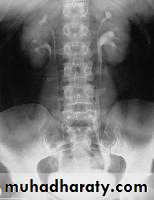

Horseshoe Kidney

found in 1:1000 necropsies an is commoner in men.

probably the most common of all renal fusion anomalies

The anomaly consists of two distinct renal masses lying

vertically on either side of the midline and connected at

their respective lower poles by a parenchymatous or fibrous

isthmus that crosses the midplane of the body.

Fusion of the renal masses early in embryonic life, so its ascent

will be impeded by inferior mesenteric artery.

The kidneys are low located, mal rotated and pelves lie anteriorly

Symptom When present, they are related to complications like hydronephrosis, infection, or calculus formation

Diagnosis ultrasound, IVU, CT scan